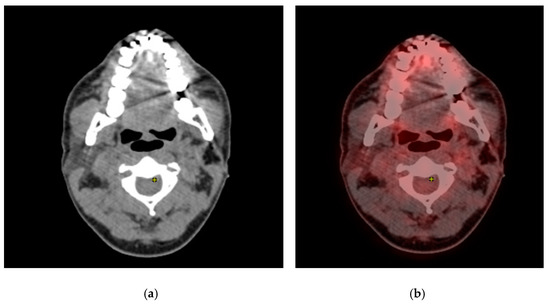

Even then, PET-CT might show false positive results in a review patient who poses diagnostic confusion. One such case is presented here: A 58-year-old male patient was diagnosed and treated for salivary gland ductal carcinoma by surgery and radiotherapy one year prior to this event. In the review CT, brain metastasis was evident. A PET-CT was advised immediately, and PET-CT revealed metastasis to the lung nodules as well.

In addition to the signals in the metastatic nodules, a well-defined positive signal was evident in the submental region (Figure 10a,b). Upon clinical correlation, there was no evidence of a sign of metastasis in the submental region. This might be confused with a metastatic involvement, thus representing a pitfall.

Figure 10. (a) CT reveals hyperdense area in the submental region; (b) PET-CT reveals a well-defined positive signal was evident in the submental region, which was a false positive finding.